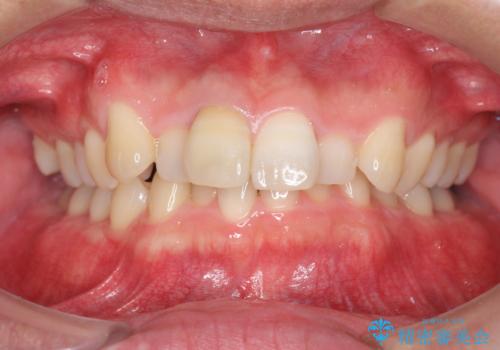

- 前歯のがたつきを改善したい、と矯正治療を希望され来院されました。

・深い噛み合わせ(ディープバイト) ・2級性の咬合関係(上顎前突)・前歯のがたつき

深い噛み合わせと上顎前突の状態を治すのに時間がかかりましたが、治療後は理想的で安定した咬合関係となりました。